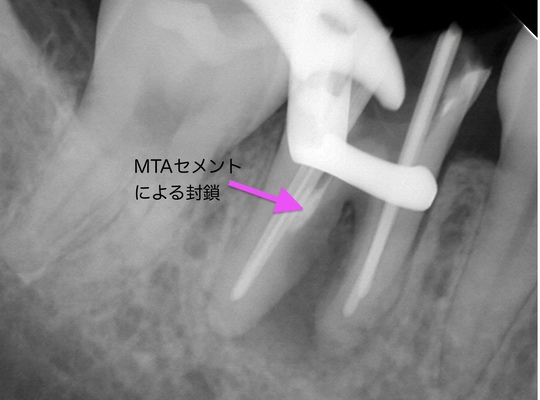

自費根管治療症例7 治療前(感染根管処置、穿孔封鎖)

「銀歯がひどく痛む」

前医の治療の時に根管に孔が空いたようです

管の途中に孔が確認できます

銀歯です

精密根管治療(自費根管治療)治療開始

精密根管治療(自費根管治療)、治療回数3回、治療期間約1週間、治療費(大臼歯再治療)15万3千円+4,500円X2回 ジルコニアクラウン6万9千円

治療後

症状は消失、補綴処置は他院にて予定。

レントゲン写真

孔はMTAセメントで封鎖しました

根管充填もMTAセメントによる穿孔封鎖もうまくいきました

根の周りの黒い影がなくなり、骨もほとんど回復して、痛みもありません

ジルコニアクラウン

治療の特徴

根管治療では、ラバーダムシートの使用、無菌的操作と生物学的な裏付けのある確実な治療が大切です。これは穿孔封鎖の場合も同様で、成功率、将来性に大きく影響します。ラバーダム防湿は必須です。MTAセメントは副作用もなく封鎖性、安定性がよく、学術的にも臨床的にも予知性の高い材料です。